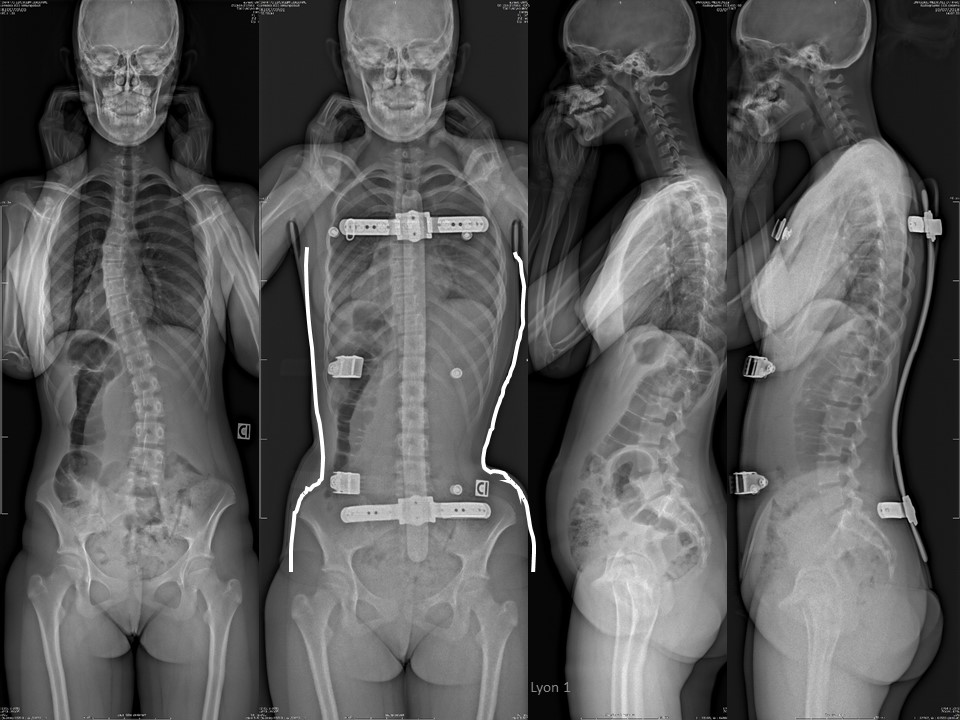

Il Metodo Lionese, il più antico dei metodi convalidati, è stato sviluppato negli ultimi 50 anni da Jean Claude de Mauroy integrando gli ultimi progressi scientifici.

Dedicato esclusivamente alle deviazioni vertebrali nei bambini e negli adulti. Portate con voi tutte le vostre radiografie. Nel caso di un CD, è necessario fare una copia cartacea, poiché la misurazione sullo schermo del computer è meno precisa.

La scansione necessaria per produrre il gesso digitale viene effettuata presso il Centro Scoliosi della Medicasud dal medico e dall'ortoprotesista che produrrà l'ARTbrace.

Da oltre 30 anni sviluppiamo sistemi CAD/CAM per lo stampaggio digitale. Solo dal 2013 i progressi della tecnologia ci hanno permesso di evitare il vecchio calco in gesso, mantenendo la correzione effettuata direttamente sul paziente. L'azienda Tombolini è all'avanguardia in questa tecnologia in Puglia.